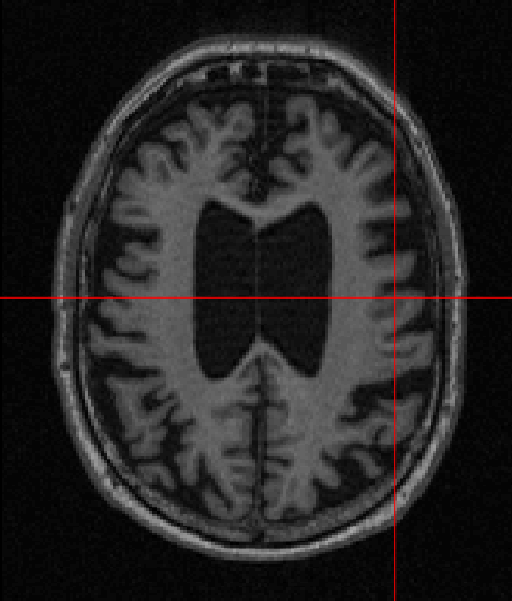

German physicist Alois Alzheimer laid the foundations of most of the modern understanding of the underlying causes of this disorder when he noticed the common biomarkers through histological techniques on the brains of his diseased patients [5]. Recent technologies exist, such as MRI, which helps in visualising atrophy or change in tissue volume of such biomarkers over a period of time, or fMRI, which can identify high-resolution activation of different brain regions during various cognitive tasks [6]. Fig. 1 shows the example of an AD patient’s raw unprocessed brain slice in different planes obtained from MR imaging in a magnetization-prepared rapid gradient-echo (MP-RAGE) sequence.

Refer to caption

(a)

(b)

(c)

Figure 1: MP-RAGE T1 Weighted MR slices: (a) Axial plane (b) Sagittal plane (c) Coronal plane